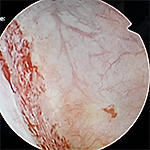

わが国では、ハンナ病変(正常の毛細血管構造を欠く特有の発赤粘膜)または膀胱水圧拡張後の点状出血の確認が重要視されています。

- 膀胱内にハンナ病変または膀胱拡張術後の点状出血を認める。